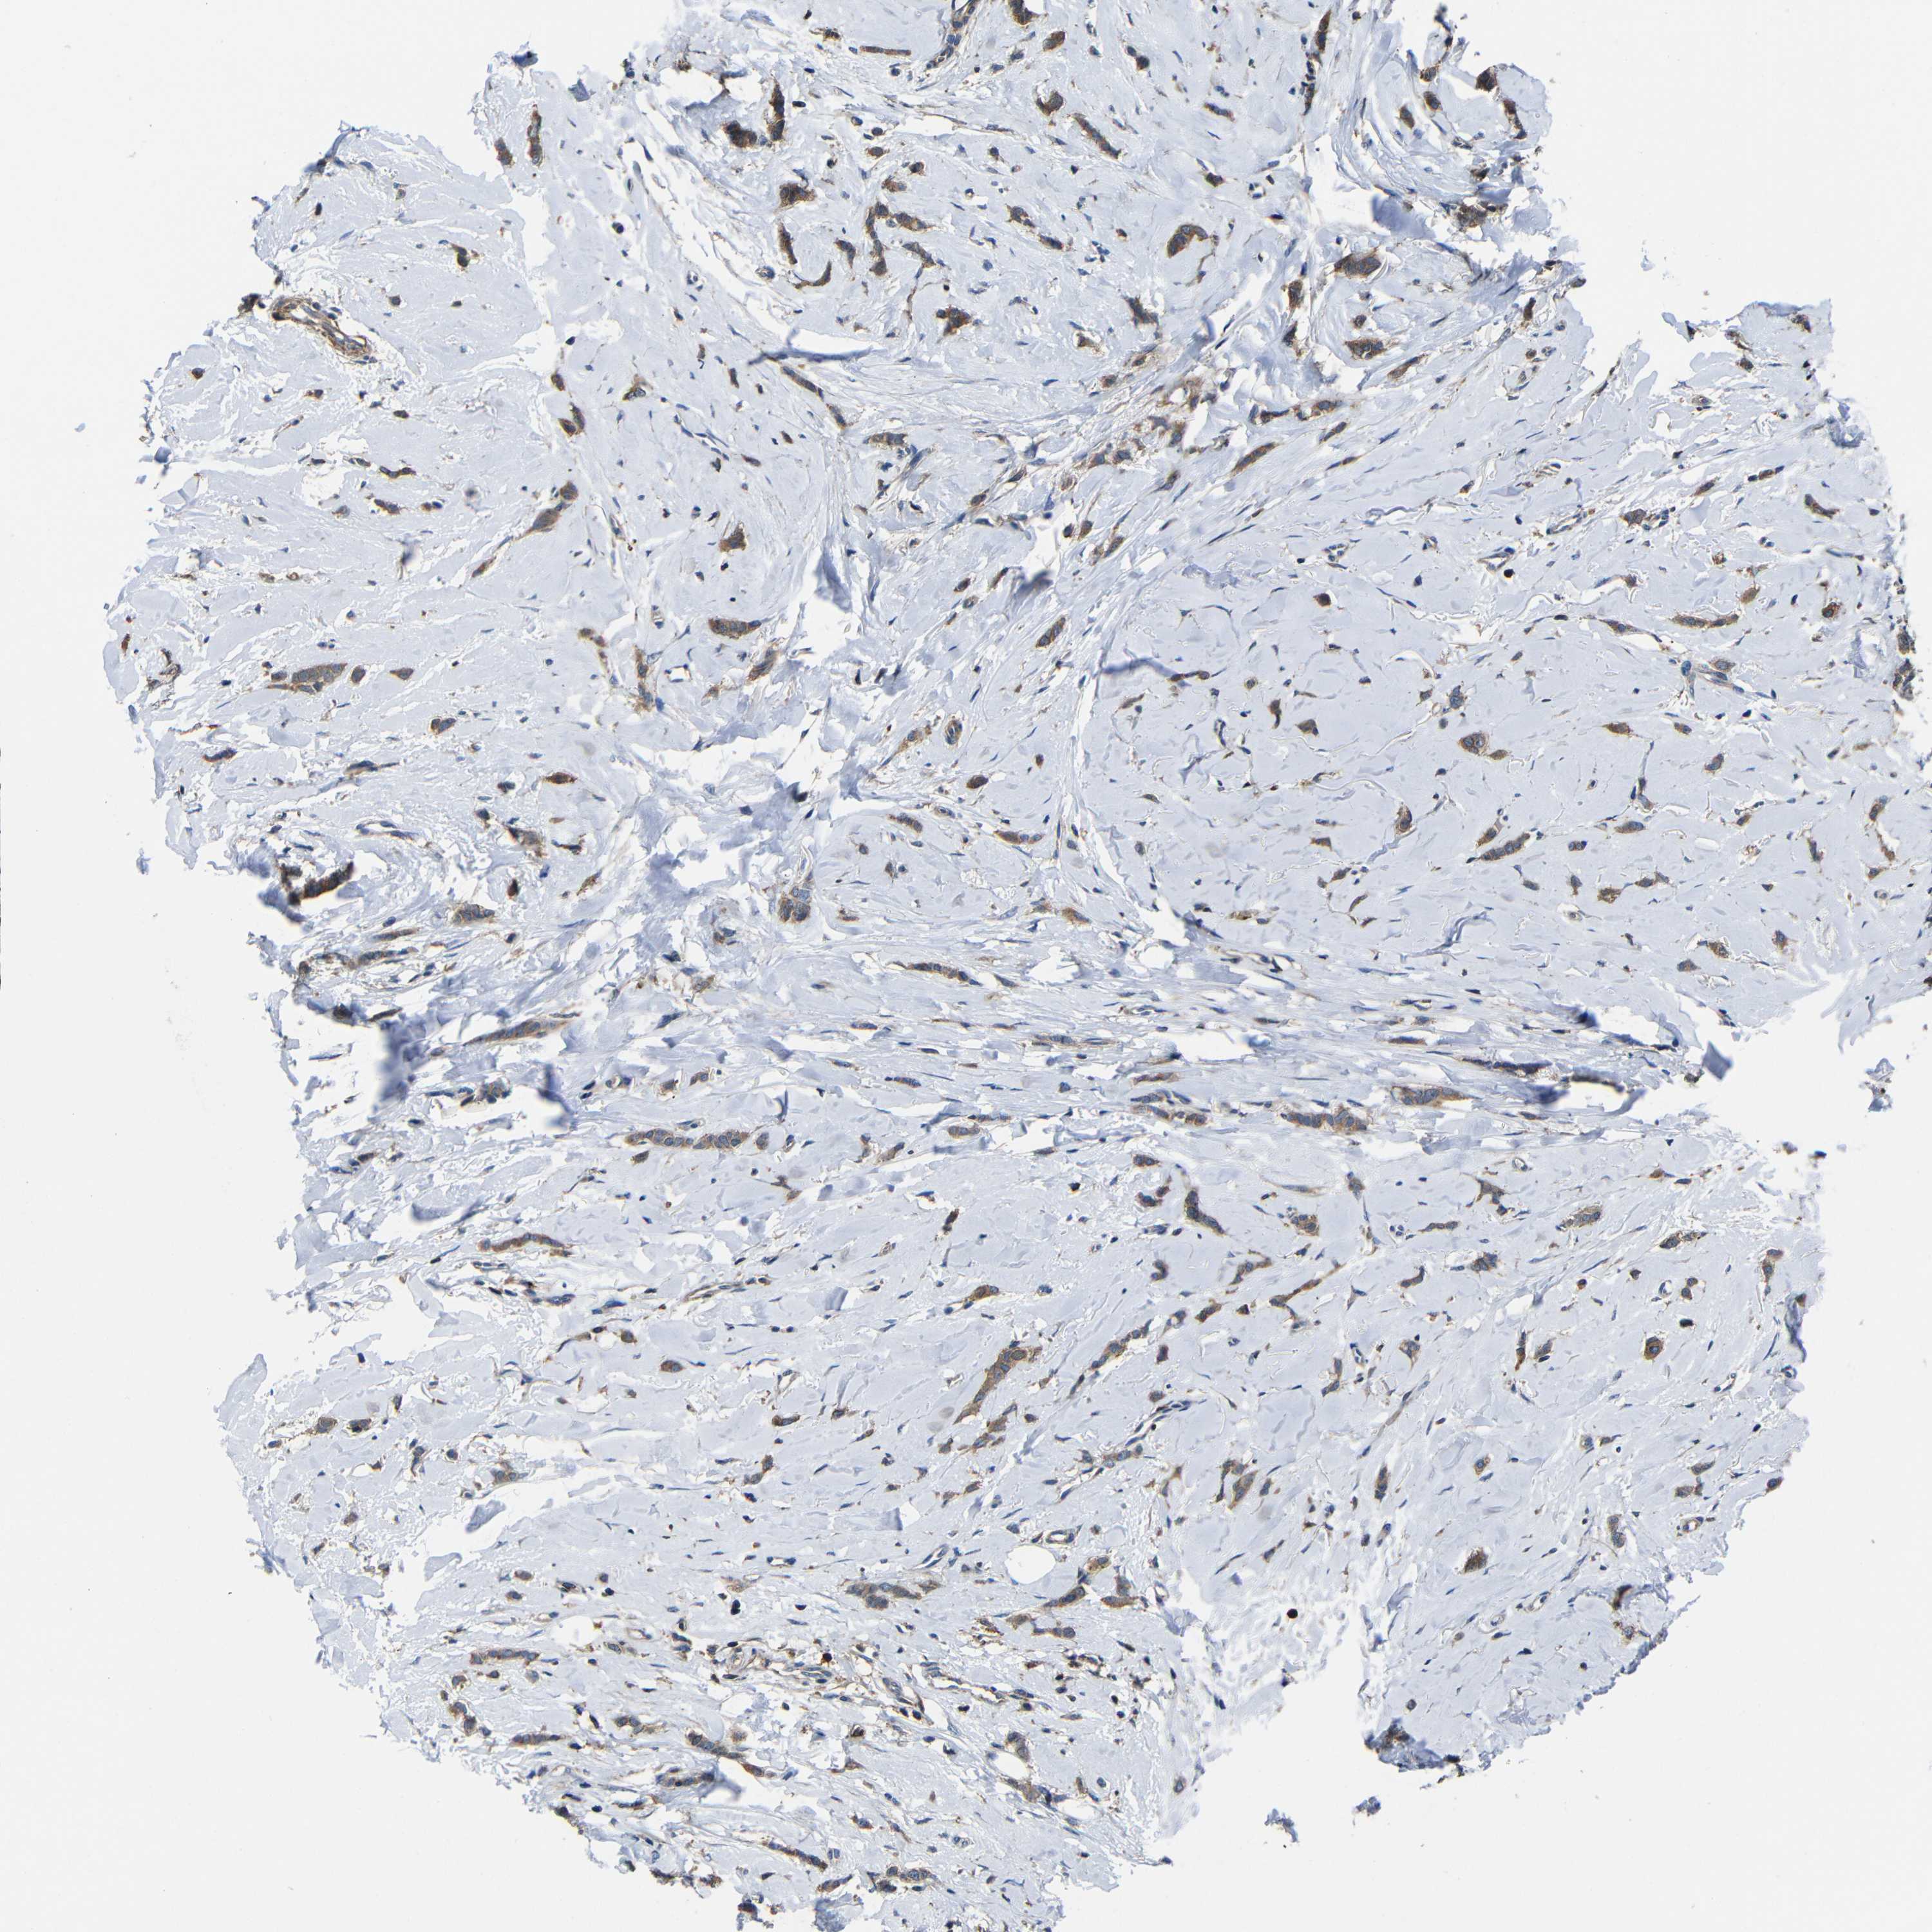

BRCA TCGA BRCA VALIDATION PROTEIN EXPRESSION

Breast cancer

Human cancer

Breast invasive carcinoma